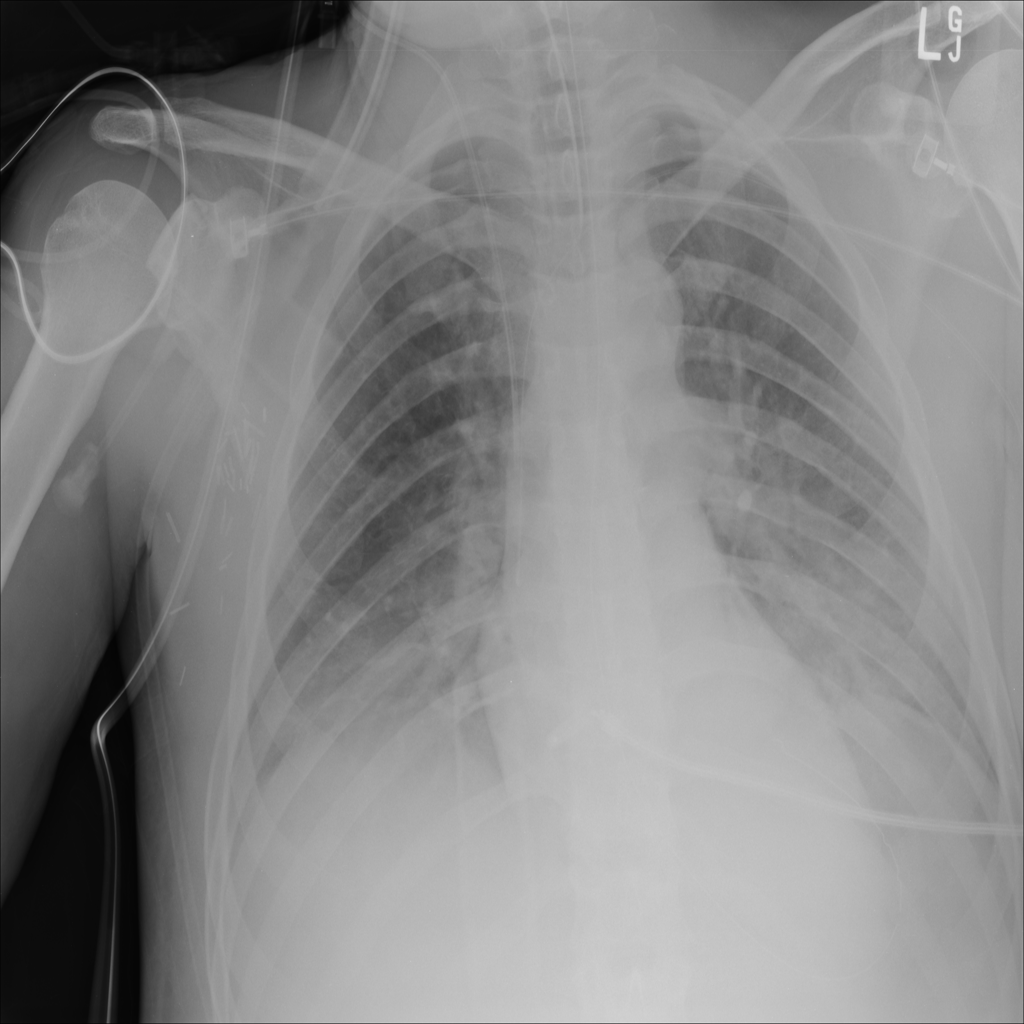

PAT-E828 · IMG-004Edema

PAT-E828 · IMG-004

AP